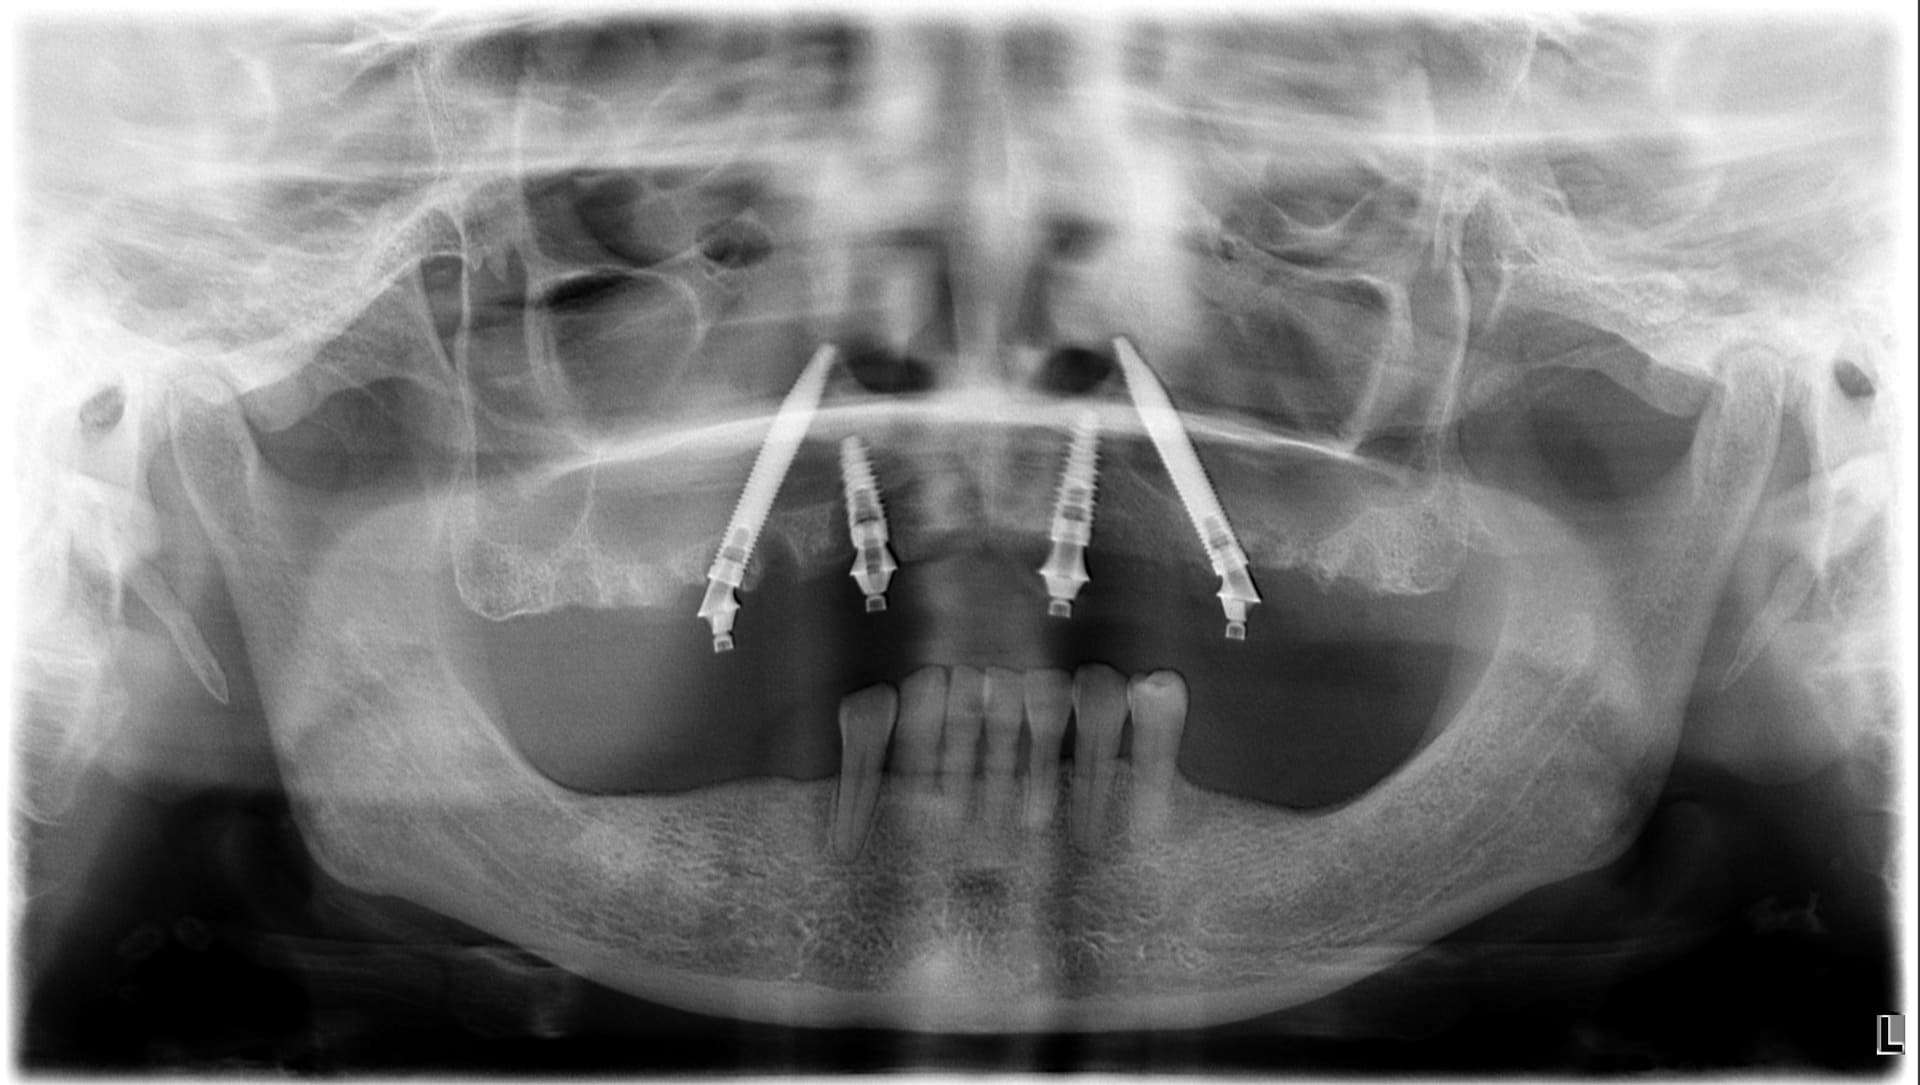

Paziente 3

< Prima

Dopo >